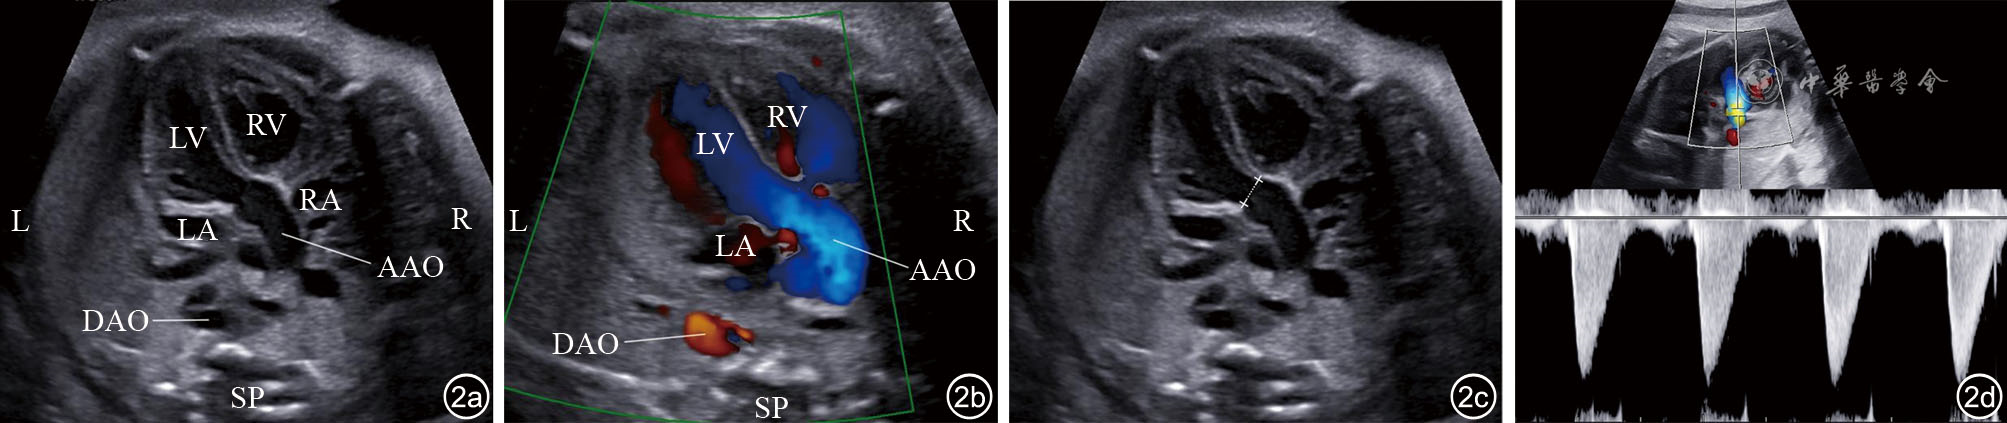

图2 左心室流出道切面超声图像和彩色多普勒血流成像(CDFI)。图a为左心室流出道切面;图b为左心室流出道切面CDFI;图c为主动脉瓣环内径测量示意图;图d为多普勒频谱图测量主动脉流速 注:LV为左心室;RV为右心室;AAO为升主动脉;LA为左心房;RA为右心房;DAO为降主动脉;SP为脊柱;R为右侧;L为左侧